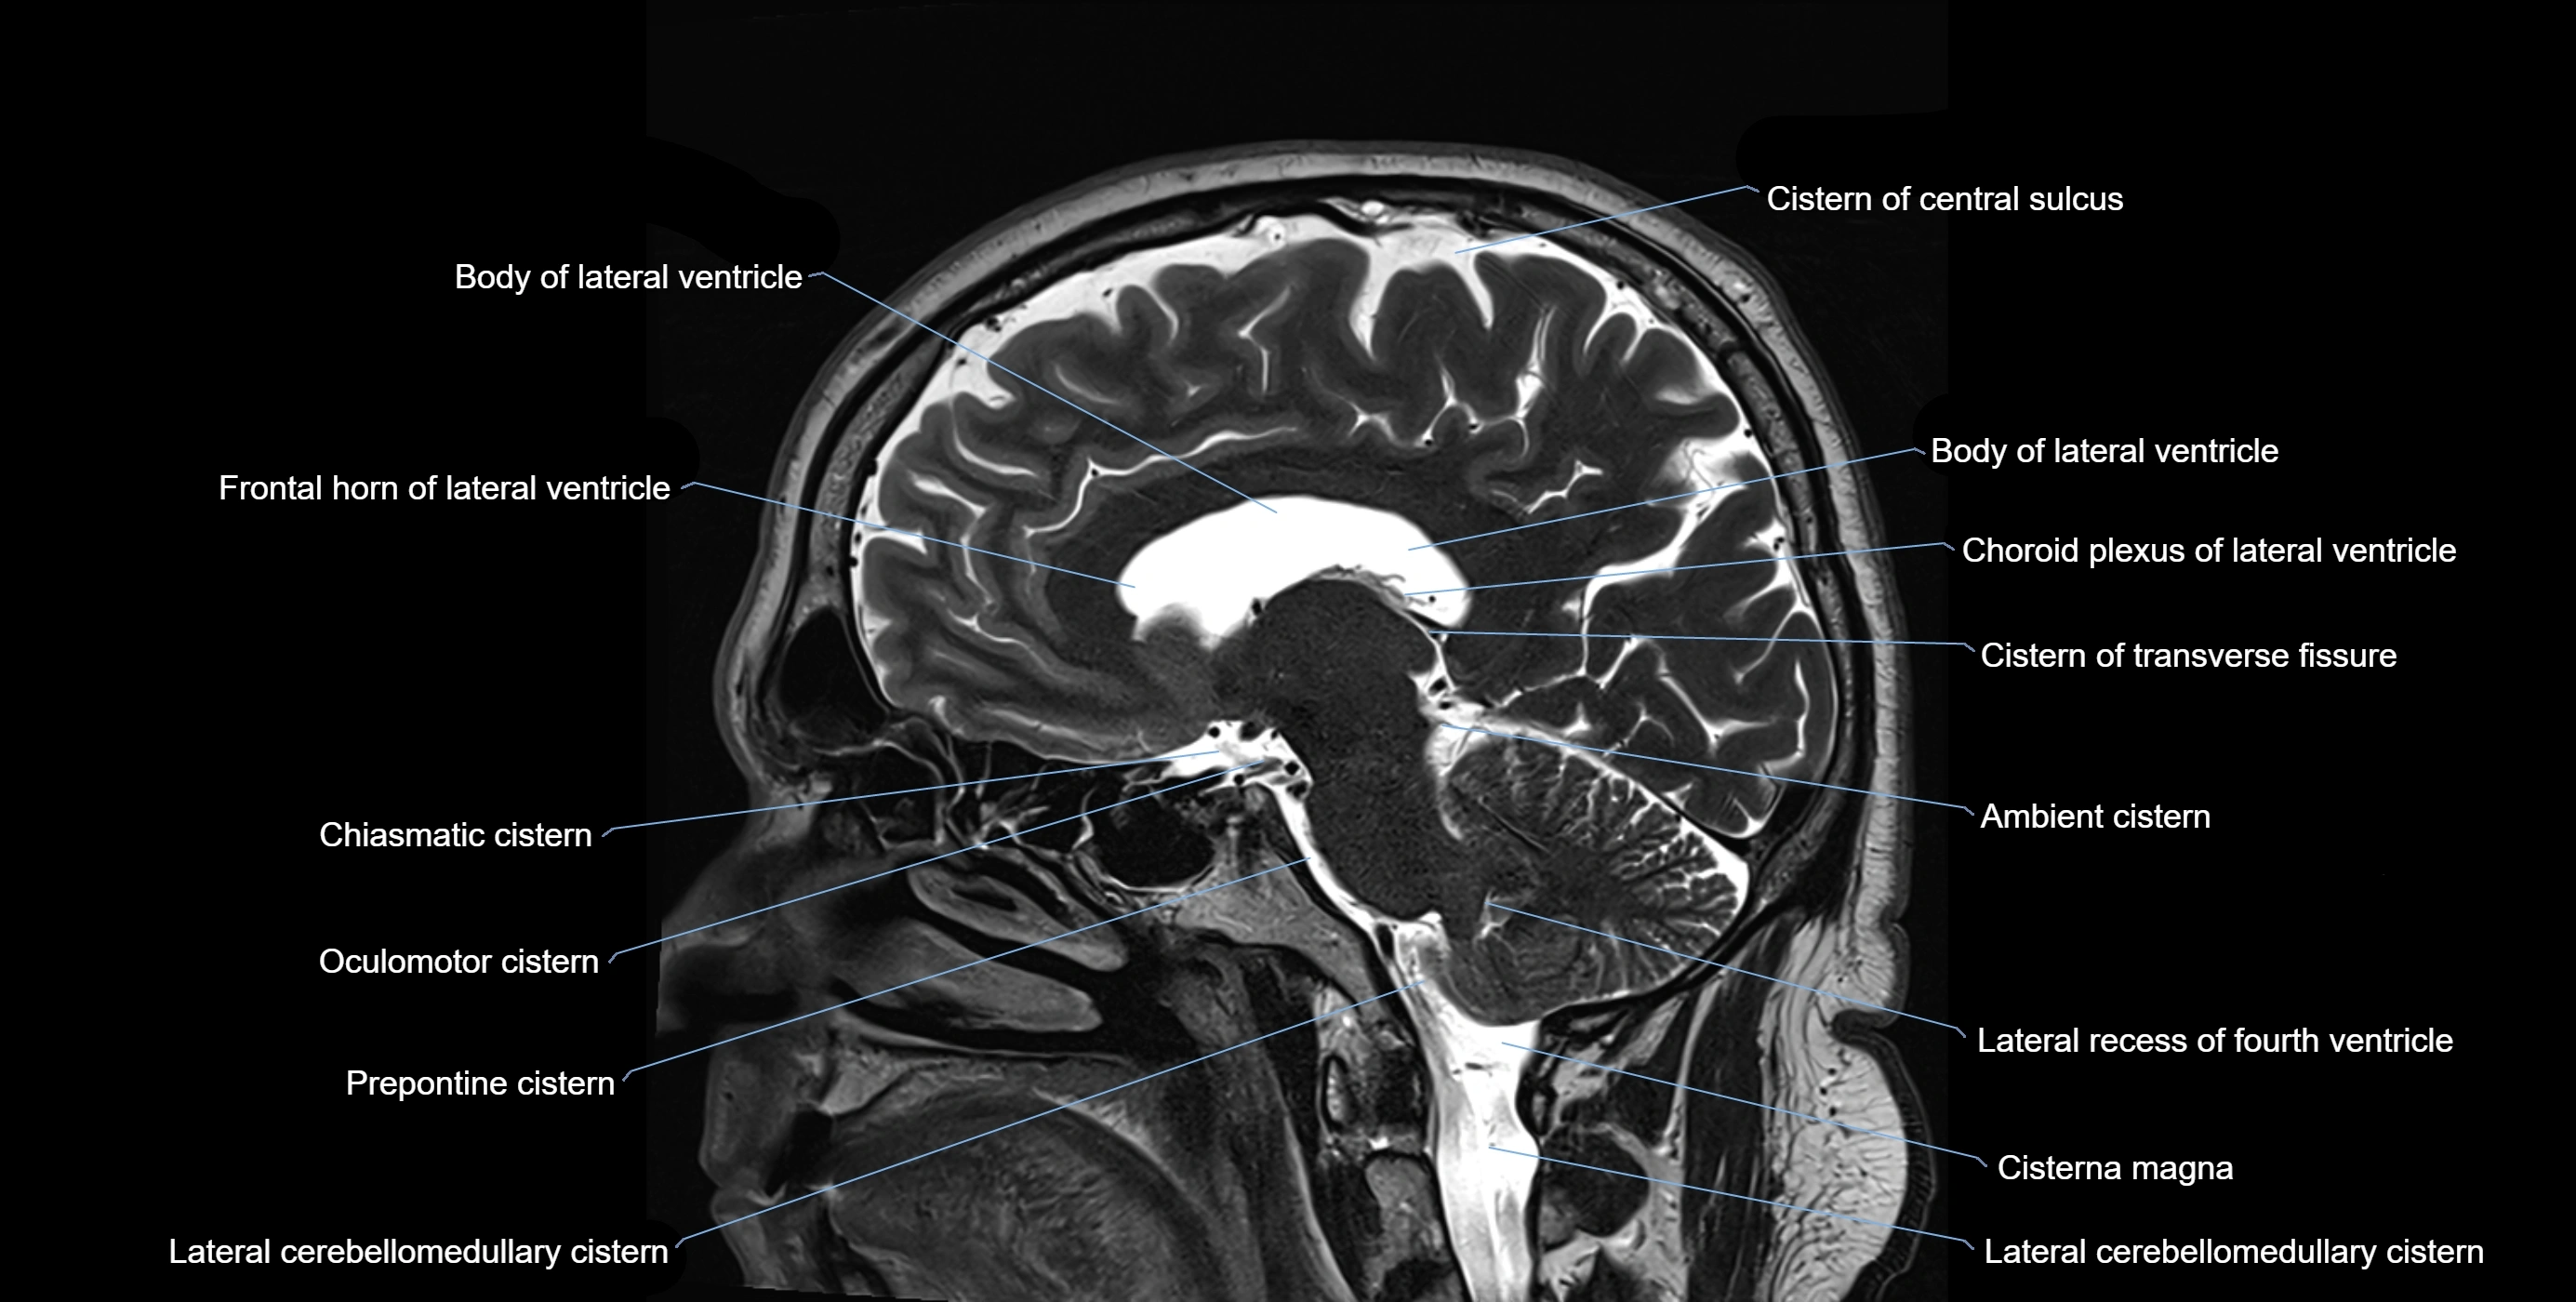

MRI images

image